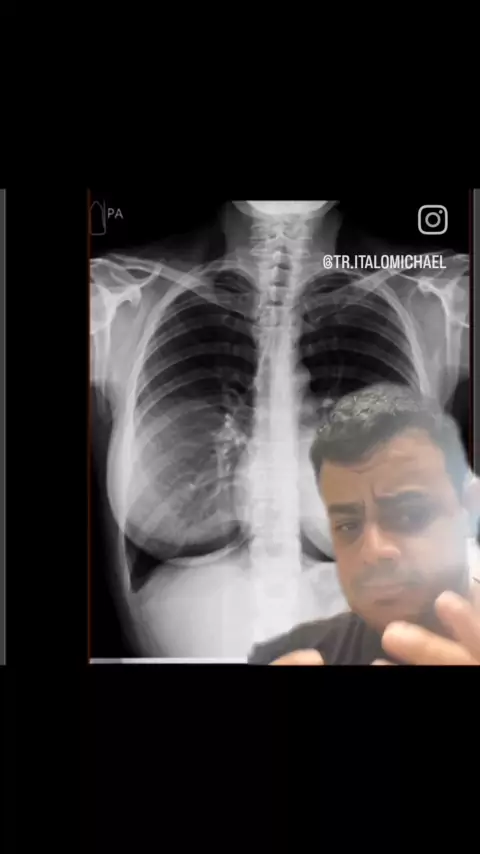

raio x de torax #med #T_Enfermagem #radiology

como carcular o índice cardiotóracico @tr.italomichael CRTR-PR 07244T #med #radiology #RaioXd #cardiologia #medicina